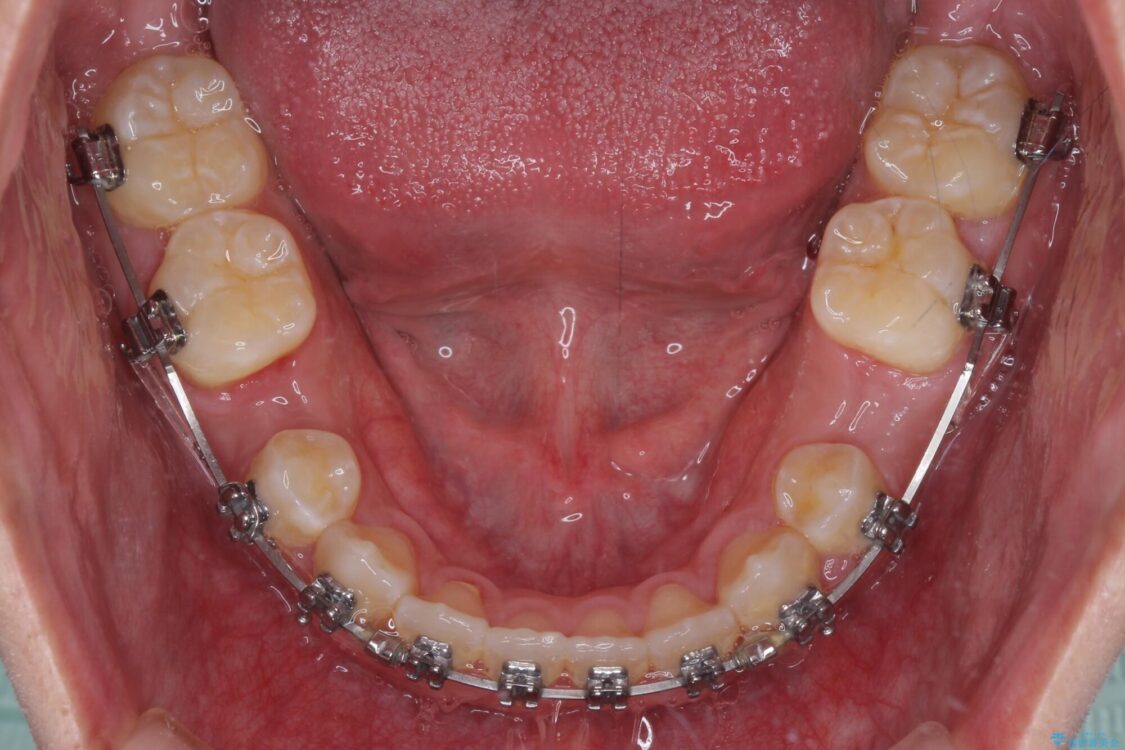

治療途中

• 口元の突出感を改善 受け口傾向の咬み合わせの抜歯矯正 治療途中画像